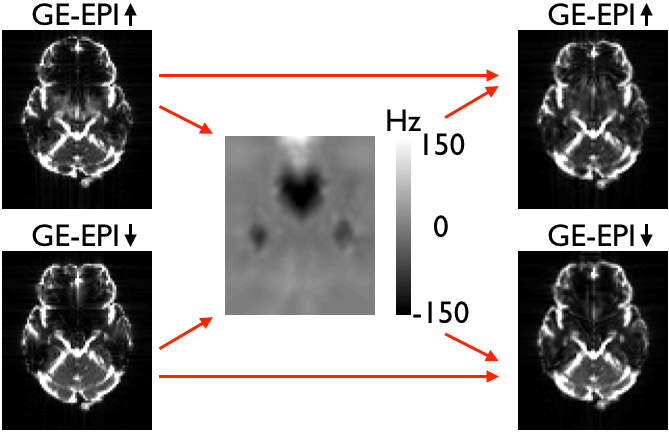

This means that the model underlying topup is not valid for these data, and the consequence will be that topup will attempt to "explain" the observed differnces due to signal modulation as being caused by distortions. It can do a surprisingly good job at that, producing two "corrected" images that look very similar. But that is potentially at the cost of an estimated field that is far from the true field, and "corrected" images that are potentially even worse distorted than to start with. Below is a comparison between a field estimated from a pair of Spin-Echo(SE)-EPI images and from a pair of GE-EPI images. The images have been simulated using the physics based MR-simulator POSSUM, so the truth is known. As can be seen the field estimated from the GE-EPI pair is almost the negation of the true field. This means of course that the "corrected" images are worse than the original images.

![]() |

| Both panels show the two original (distorted) images on the left, the field estimated (by topup) to minimise the difference between the corrected images in the middle and the two corrected images on the right. The left panel shows SE-EPI images (e.g. diffusion b0-images) and the right panel shows GE-EPI images (e.g. fMRI images). Note that topup appears to have done a good job of correcting for distortions in both cases, but that the estimated field for the GE-EPI data is almost the negation of the true field. | |

If instead using the true field for the GE-EPI images one can see below that the corrected images also look good. But looking closely one can see that in the areas of severe signal modulation it doesn't do quite as good a job (of matching the intensities) as the "faulty" field. Hence it is easy to see why topup would find the "faulty" field.